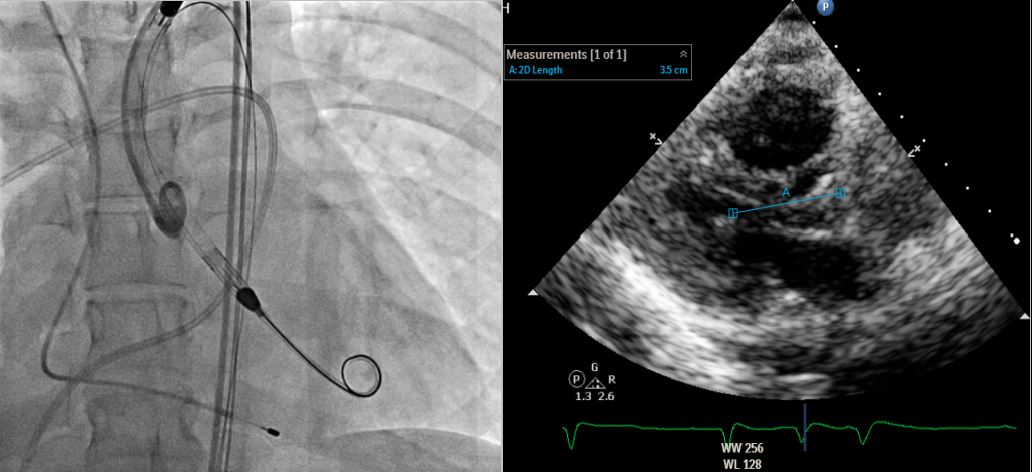

**STEP 4: Insert ABIOMED Impella CP® Microaxial Flow Catheter for Cardiogenic Shock** Pre-embedded 2 Abbott Perclose ProGlide™ SMC System sutures at right EIA sheath. Inserted Impella sheath; Advanced 0.18 wire to LV with pigtail, and checked Impella CP device for function and primed with saline. Positioned Impella tip in LV using fluoroscopy; removed guidewire and connected to console. Confirmed Impella function; secured access site.

**STEP 5: Removal of Impella on Day 5** Removed Impella after inserting 0.35 J-tip wire to aorta; Achieved hemostasis using ProGlide™ sutures.

**STEP 4: Insert ABIOMED Impella CP® Microaxial Flow Catheter for Cardiogenic Shock** Pre-embedded 2 Abbott Perclose ProGlide™ SMC System sutures at right EIA sheath. Inserted Impella sheath; Advanced 0.18 wire to LV with pigtail, and checked Impella CP device for function and primed with saline. Positioned Impella tip in LV using fluoroscopy; removed guidewire and connected to console. Confirmed Impella function; secured access site.

**STEP 5: Removal of Impella on Day 5** Removed Impella after inserting 0.35 J-tip wire to aorta; Achieved hemostasis using ProGlide™ sutures.

We report a youngwoman with fulminant myocarditis, who survived with temporary Impella CP® support. An initial ECG showed ST elevation in V1 and aVR, indicatingpossible right ventricular involvement. For circulatory support, wechosed Impella CP® because VA-ECMO would increase afterload, leadingto pulmonary edema and poor LV recovery. Even RV was involved withimpaired RV function, her clinical condition remained stable underthe treatment guided by PAC. By day 3, her cardiac function hadimproved much, and the Impella CP® was removed on day 5. The patient wasdischarged on day 11. One-month follow-up showed full RV and LVrecovery.